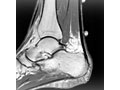

Resonancia magnética. Se puede usar para revisar el tendón y ver si hay señales de tendinopatía o desgarro del tendón. También se utiliza una resonancia magnética para evaluar el hueso del talón.